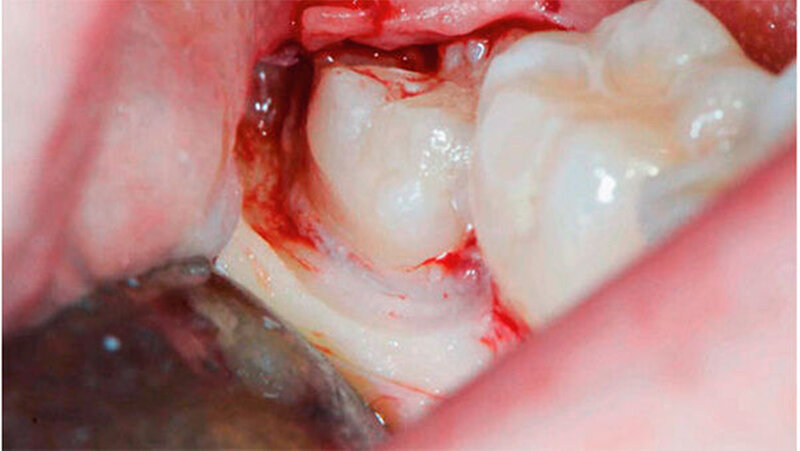

Die Koronektomie wurde, wie in Abbildungen 1a bis k gezeigt, durchgeführt. Die Schnittführung erfolgte intrasulkulär beim Nachbarzahn mit kurzer disto-bukkaler Entlastung über dem Ramus ascendens. Anschließend wurde ein bukkaler Mukoperiostlappen gebildet. Die Zahnkrone, welche von Knochen bedeckt war, wurde mit dem Handstück und dem Rosenbohrer unter ständiger NaCl-Kühlung bis zur Schmelz-Zement-Grenze freigelegt.

Anschließend wurde mit einem Fissurenbohrer die Krone an der Schmelz-Zement-Grenze abgetrennt. Es wird empfohlen, den Fissurenbohrer nur so weit in den Zahn vordringen zu lassen, dass die lingualen Weichgewebe nicht verletzt werden.

Danach wurde die Krone mit dem Hebel abgetrennt. Dabei ist darauf zu achten, dass die Wurzel nicht anluxiert wird. Falls der Wurzelblock nach dem Dekapitieren eine verstärkte Mobilität aufweisen sollte, muss aufgrund einer erhöhten Infektionsgefahr eine komplette Extraktion durchgeführt werden.

Sobald die Krone abgelöst war, konnte mit einem Rosenbohrer unter ständigem Schutz der lingualen Weichgewebe mittels Raspatorium verbleibender Schmelz abgetragen werden. Der Wurzelblock sollte einige Millimeter unterhalb der bukkalen Knochenkante abgetragen werden. Anschließend wurden scharfe Zahn- und Knochenkanten geglättet. Die Pulpa bedarf keiner weiteren Behandlung.

Nach Kürettage und Spülung mit NaCl-Lösung wurde der Lappen reponiert und ein primärer Wundverschluss durchgeführt (Supramid 4–0, B Braun Medical AG, Sempach, Schweiz). Zur Analgesie wurde der Patientin Mefenaminsäure 500 mg (Mefenacid, Streuli Pharma AG, Uznach, Schweiz) dreimal täglich verordnet.